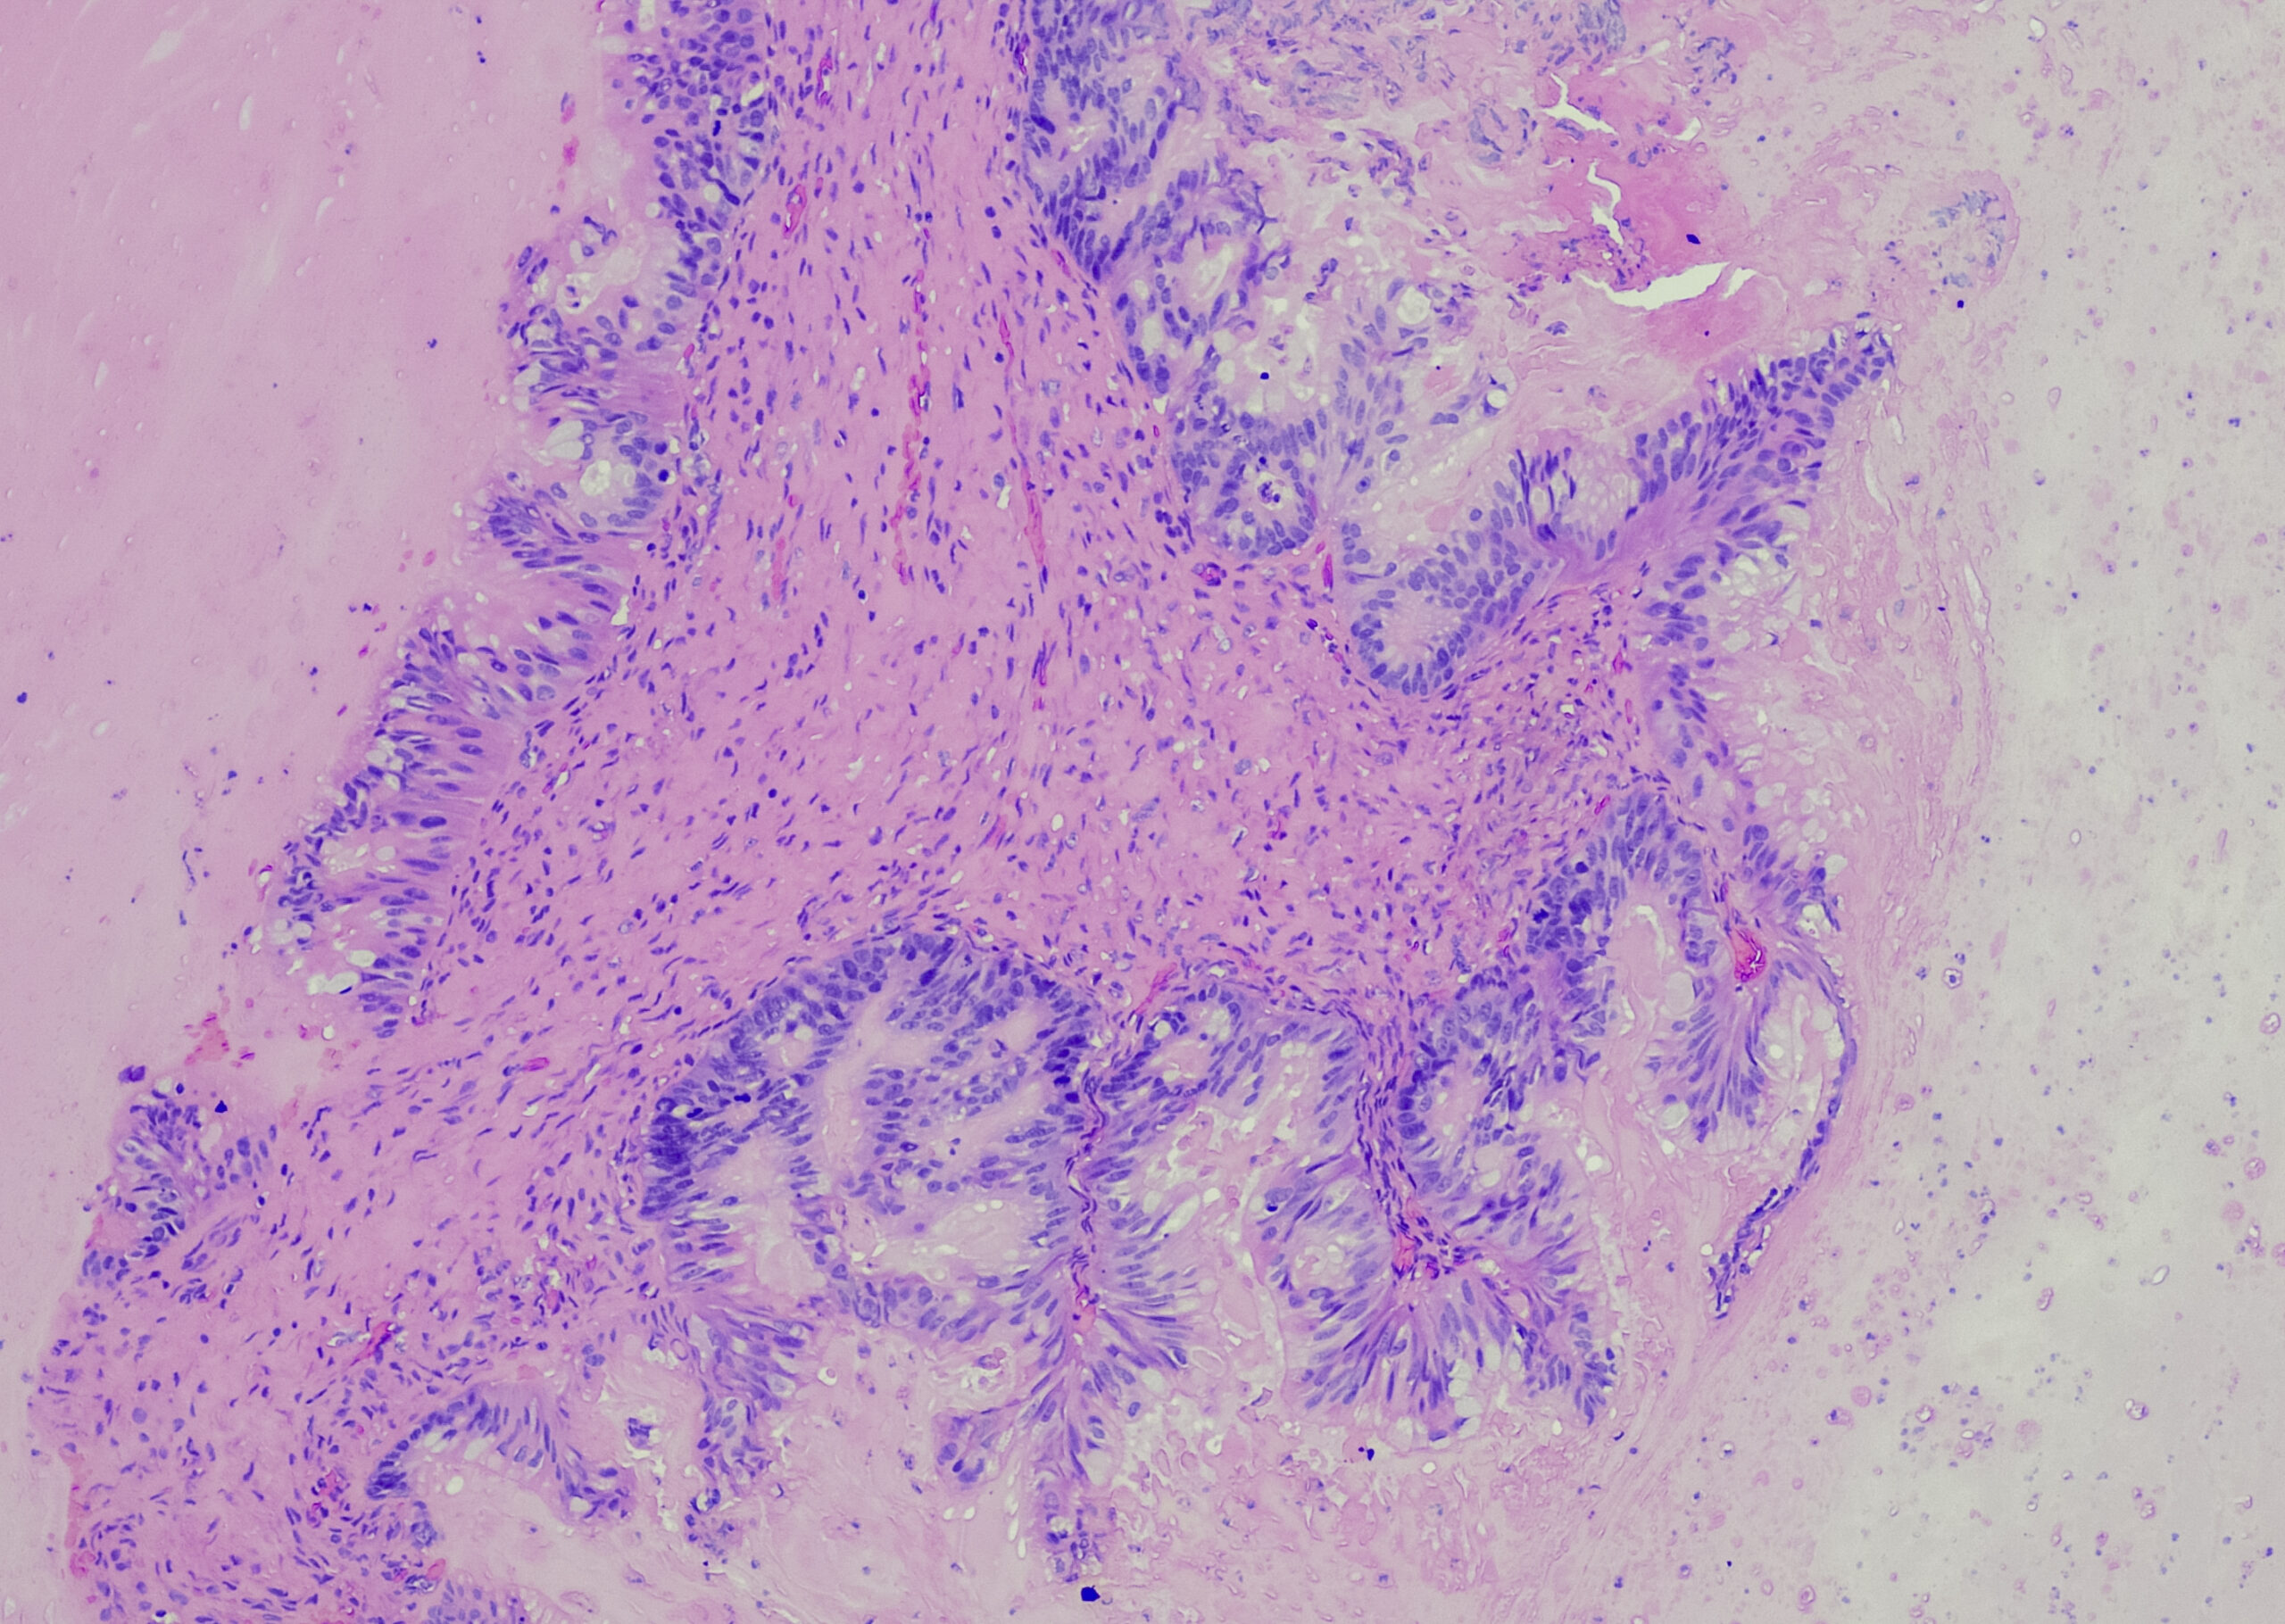

Molekulare Vielfalt des PDAC

• Gastroenterologie und Hepatologie

• Genetik

• Onkologie